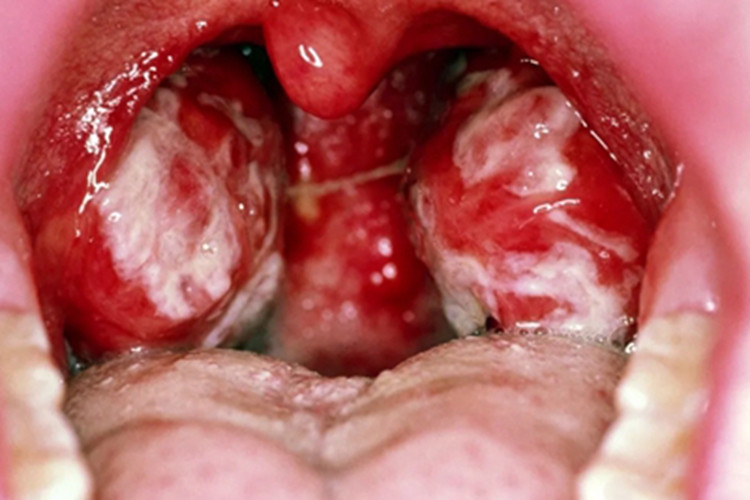

急性滤泡性扁桃体炎发作时,扁桃体充血、肿胀,严重时化脓,表现为局部出现脓液,可呈黄白色。同时患者可有吞咽疼痛、吞咽困难、异物感等症状。